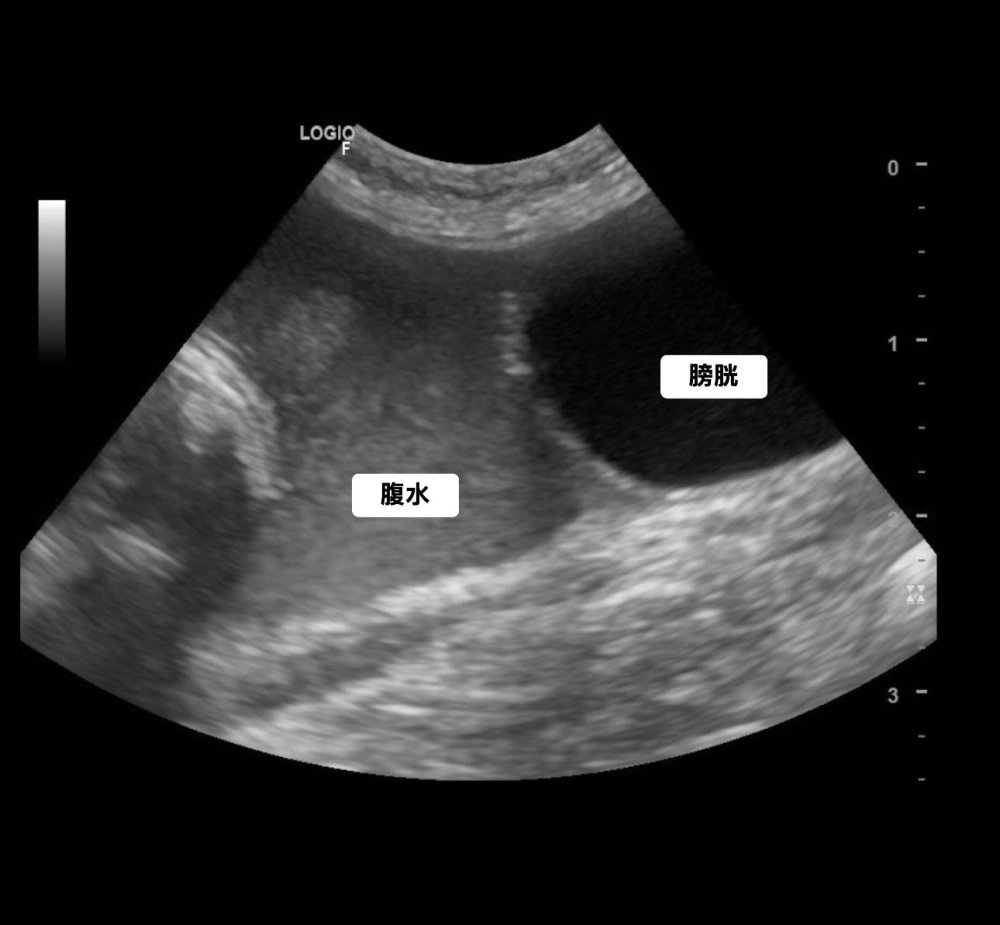

橘白小貓小虎突然肚子鼓鼓的,飼主以為是變胖,結果發現牠精神差、食慾不好,到院後一照超音波,腹腔裡滿滿的腹水!

(病例一)超音波掃描可見腹水,抽出檢驗發現其蛋白含量高,冠狀病毒PCR陽性,確診為傳染性腹膜炎。

(病例一)經過一週治療 已經無腹水 貓咪精神食慾也有改善